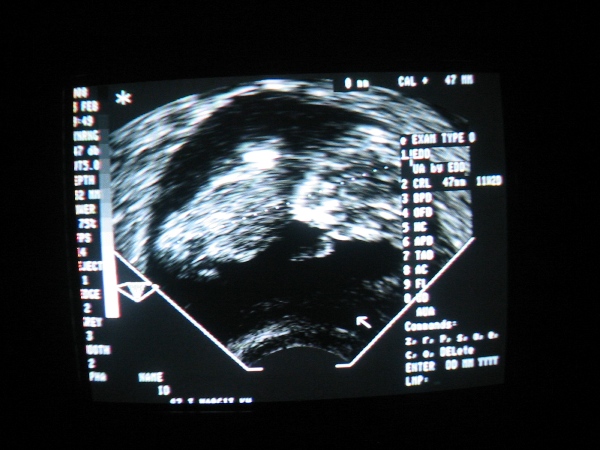

Az új babaképekhez gratulálok, nagyon édesek!már úgy várom a hétfőt, hogy én is meglessem.